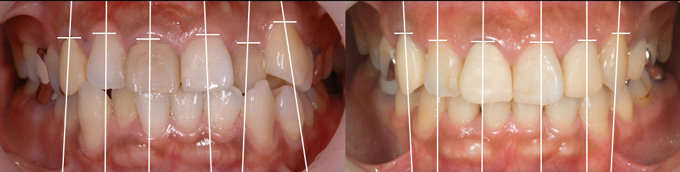

左下:全ての歯に多くの茶色い歯石が付着している、歯石で歯と歯の間が埋まっていることから歯槽骨の喪失も疑われます。

右下:歯石除去をし、歯肉の炎症がとれ引き締まった状態、結果的に治癒とともに歯と歯の間の歯茎の隙間が生じています。

BEFORE(歯周基本治療前)

AFTER(歯周基本治療後)

写真では見えている歯石しか確認できませんが、レントゲンを取ってみると歯肉で見えない部分まで歯石が付いているのがわかります。

BEFORE(歯周基本治療前 レントゲン)

AFTER(歯周基本治療後 レントゲン)